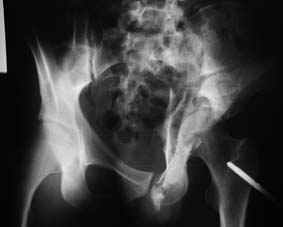

Re: Повреждение вертлужной впадины 2,5 мес.

Это обзорные и косые снимки